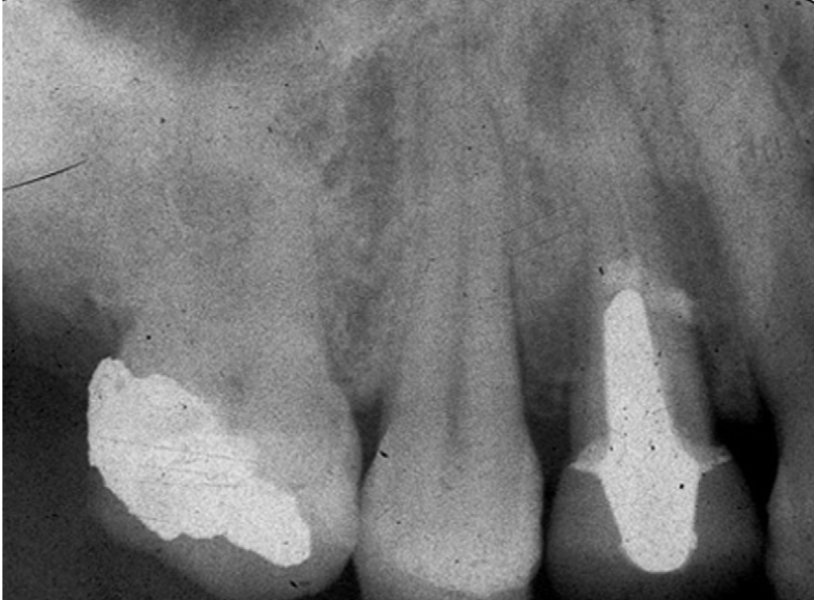

The above picture is a radiograph of a patient who attends your surgery with a toothache.She complained of dull aching pain on the upper right, with some tenderness in the upper buccal sulcus. The pain is unaffected by thermal stimuli. Describe your assessment and likely diagnosis.

The radiograph shows a large restoration in the molar and a post crown on the first premolar. In the premolar, the root filling looks insubstantial and there is a periapical granuloma present. At the level of the end of the post, there is radio-opaque material overlying the tooth and bone. Also at this level and further coronally, lamina dura is lost along the root surface.

The lack of any aggravation of the pain by thermal stimuli suggests that this is not pulpitis. The dull aching pain, along with the tenderness in the buccal sulcus, suggests chronic periapical periodontitis is a likelier diagnosis. On radiological grounds, there is only one likely tooth with problems: the first premolar. The apical granuloma suggests chronic inflammation, but you should bear in mind that the radiograph is a snapshot in time and that the lesion could be healing (although the poor root filling suggests otherwise). The interesting finding is the collection of signs around the end of the post. The radio-opaque material overlying the root here is probably extruded cement from when the post was cemented. This at least suggests a perforation and may indicate a fracture of the root at this level. Clinical examination might reveal mobility of the crown if a fracture were present